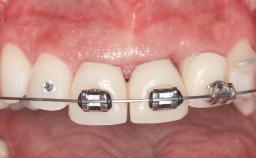

Replacement of Four Incisors with a Fixed Partial Denture on Two Narrow-Neck Implants after Implant Failure

| Prosthesis Type | FDP |

| Retention | Screw-retained, with splinted implants Screw-retained, with splinted implants |